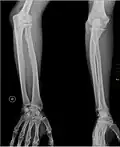

Кости предплечья, вид спереди

Кости предплечья, вид сзади